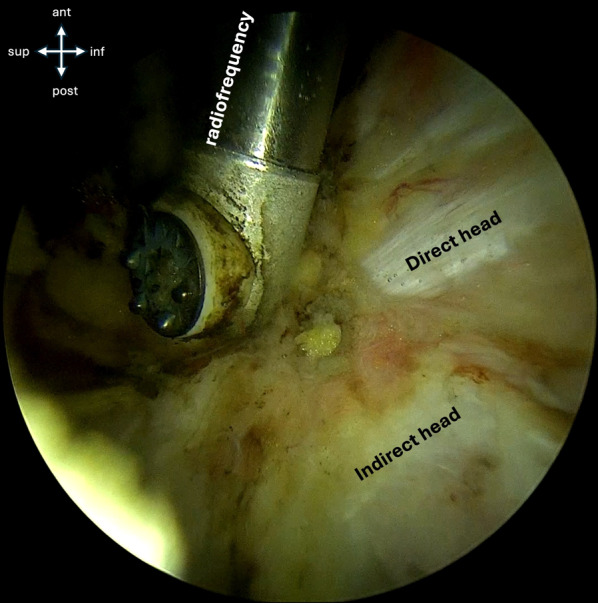

Introduction: Anterior inferior iliac spine (AIIS) avulsion fractures commonly occur in adolescent patients during sports activities. To systematically evaluate fracture severity and guide management, an adaptation of the Hetsroni classification system was used to categorize fractures on the basis of their displacement relative to the acetabular rim. Traditional open reduction and internal fixation reported satisfactory consolidation rates but complications such as lateral femoral cutaneous nerve (LFCN) neuropathies, heterotopic ossifications (HO), and subspine impingement. The objectives of this work are to (1) report short- and mid-term radiographic and clinical outcomes and (2) propose an adapted classification system based on the risk of subsequent subspine impingement.

Materials and methods: A prospective cohort study was conducted on patients with AIIS avulsion fracture with ≥ 1.5 cm displacement who underwent surgery between 2021 and 2024. Patients with follow-up < 6 months, displacement < 1.5 cm, comminuted fractures, or chronic fractures were excluded. Clinical outcomes, including the subspine impingement test, the modified Harris Hip Score (mHHS), and the University of California Los Angeles Score (UCLA), were evaluated at last follow-up. Postoperative complications, such as LFCN neurapraxia, HO (classified by Brooker), and surgical revisions, are reported.